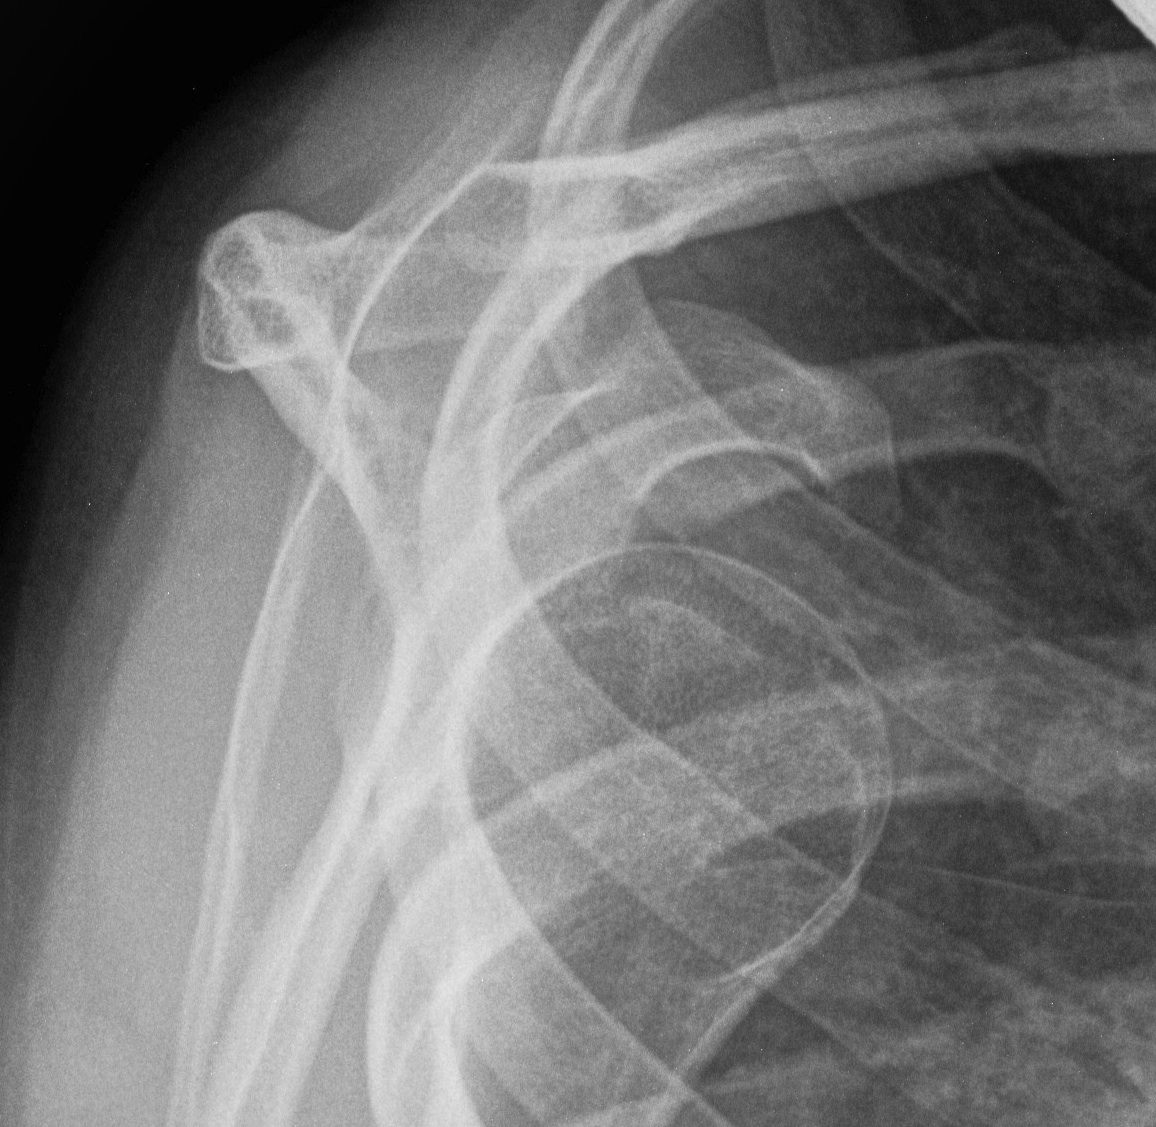

Xray

Signs of chronic shoulder dislocation